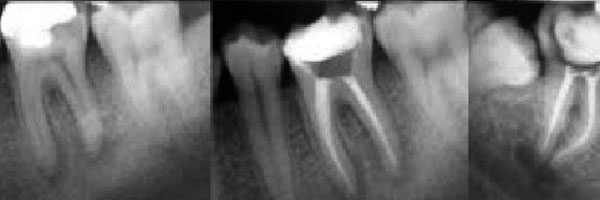

Podríamos decir que la endodoncia tiene dos fases:

1. Limpieza y desinfección del sistema de conductos: tras conocer el historial médico y anestesiar correctamente el diente a tratar, se realiza una apertura a través de la cual accedemos a la cámara pulpar; una vez allí localizamos y conformamos los conductos mediante unos instrumentos llamados limas, entre lima y lima utilizamos unos irrigantes capaces de desinfectar, disolver y eliminar todos los restos pulpares y bacterianos que vamos desbridando. Según el diente que tratemos podemos encontrarnos con 1,2, 3, 4 o incluso más conductos, muchos de ellos incluso interconectados. Tampoco todos los conductos son rectos, la gran mayoría tienen curvaturas y algunas pueden ser realmente difíciles de tratar.

2. Obturación y sellado tridimensional del sistema de conductos: su objetivo es conseguir un sellado hermético del conducto desde la parte coronaria hasta la terminación apical para que los microorganismos no vuelvan a entrar en el conducto y lo reinfecten, creando a su vez un ambiente favorable para que haya una cicatrización de los tejidos periapicales. Como material se utiliza habitualmente la gutapercha (polímero similar al caucho, derivado de un exudado vegetal).